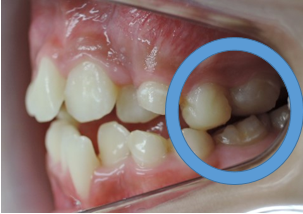

大人の矯正治療は出来るだけ見えにくい小さな矯正装置を利用して上の歯並びから歯ならび治していきます。埋伏している犬歯も萌出させていきます。

上顎の歯列がある程度改善してから下顎の歯列を見えにくいブラケットという矯正装置で整えていきます。埋伏している犬歯も萌出させていきます。

MEAW(マルチループ)により咬合高径(咬み合わせの高さ)を改善して美しい咬み合わせに治療していきます。(矯正開始から3カ月後)

終了時2か月前(1年3ヶ月後)

終了時(開始から1年8カ月後)